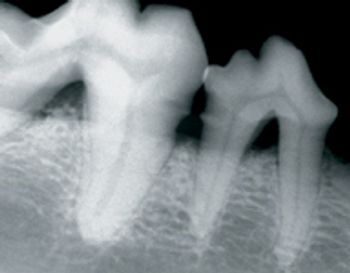

Intraoral radiographs are essential to perform quality dental therapy. Teeth can be cleaned and polished without seeing radiographic images below the gingiva, but "dentistry" cannot be performed properly.

At least 10-percent bone loss must be present to notice periapical disease radiographically.